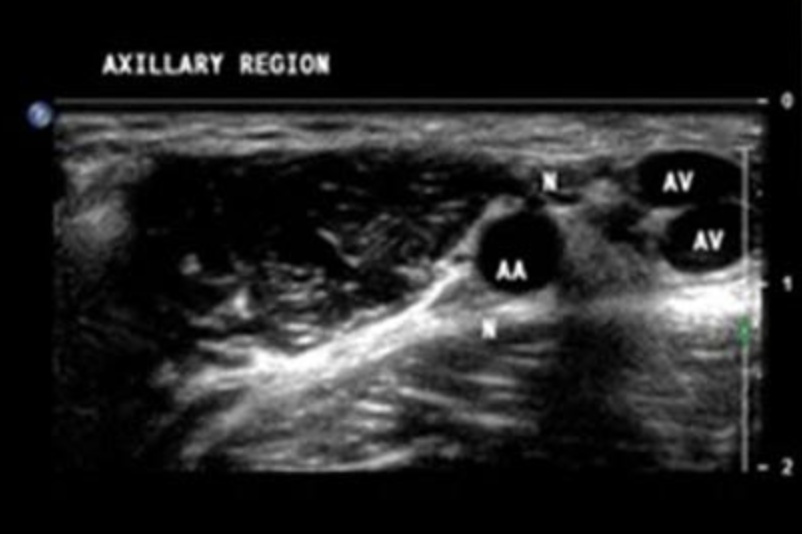

Name the structures on this US of the axilla

N – Nerve

A(X)V – Axillary vein

A(X)A – Axillary artery